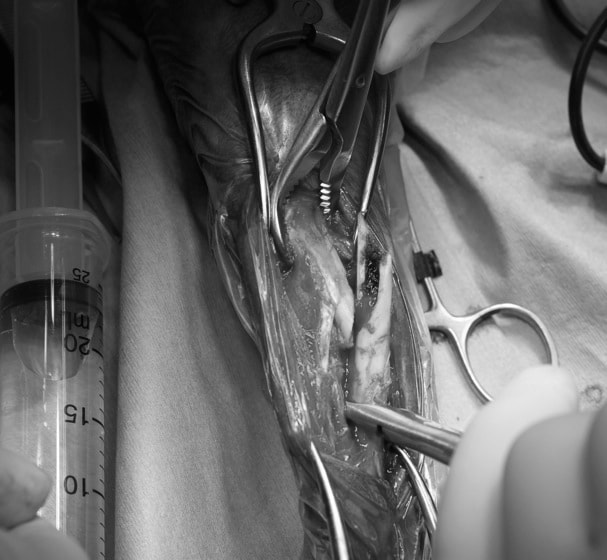

脊髄の減圧、脊柱管の再構築・安定化を目的に、片側椎弓切除術およびMatrixMANDIBLE Plateによる椎体固定を実施しました。

隣接椎体を架橋するようにプレートを設置しました。

術後レントゲン写真